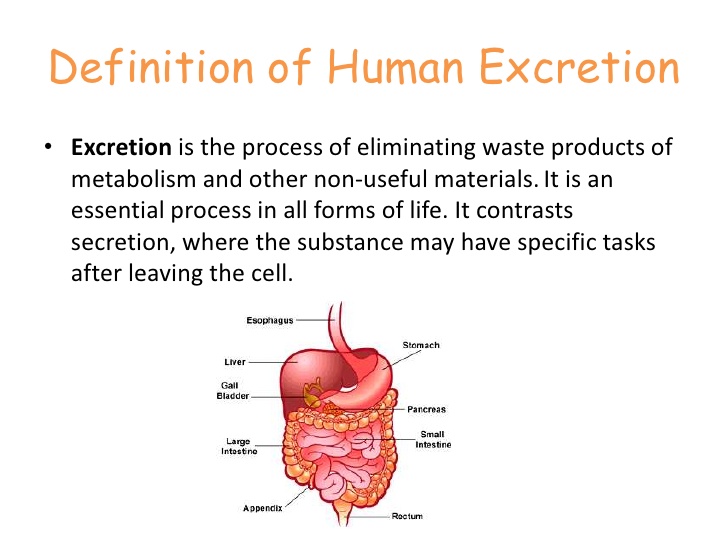

- Meaning and definition of excretion

- Excretory organs and their functions e.g. kidney, skin and lungs.

- The process of excretion.

- Waste materials of excretion e.g. carbon (iv) oxide, sweat and urine.

- Need for excretion.